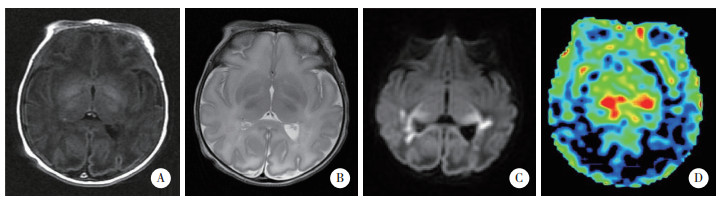

2 结果 2.1 3组ASL磁共振灌注成像检查结果所有患儿均获得满意图像。结果显示,轻度组中5例rCBF图像无显著变化,8例脑白质区灌注信号强度增高,见图 1。中度组中7例rCBF图像无显著变化,18例脑白质区灌注信号强度增高,11例脑灰质区灌注信号强度增高,14例基底节区和丘脑区灌注信号强度增高,见图 2。重度组中4例脑白质区灌注信号强度增高,3例脑灰质区灌注信号强度增高,2例基底节区灌注信号强度增高,2例丘脑内灌注信号强度增高,见图 3。

| A~C,常规MRI,双侧侧脑室旁及胼胝体区可见多发斑片状短T1短T2信号影,弥散加权呈高信号;D,ASL,脑灰质区及白质区灌注信号强度增高. 图 3 重度组典型病例MRI及ASL图像 |